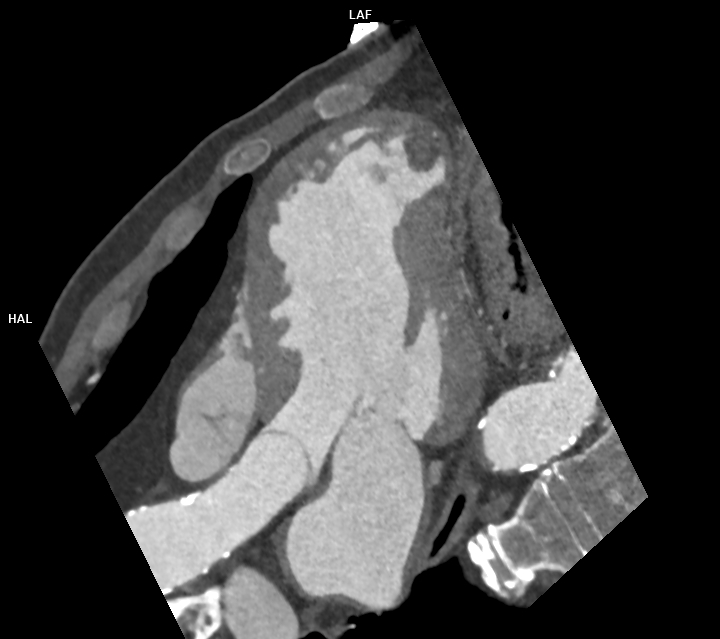

Figura 3: reconstrucție mutiplanară 4 camere din achiziție angioCT coronariană cu sincronizare ECG

Discuţie caz nr 120: Achiziția angioCT coronariană cu sincronizare ECG evidențiază ocluzie a arterei descendente anterioare în segmentul mediu cu hipokinezie severă / diskinezie a miocardului deservit și formarea unui anevrism antero-septal și apical ventricular stâng ce este locuit de un tromb.